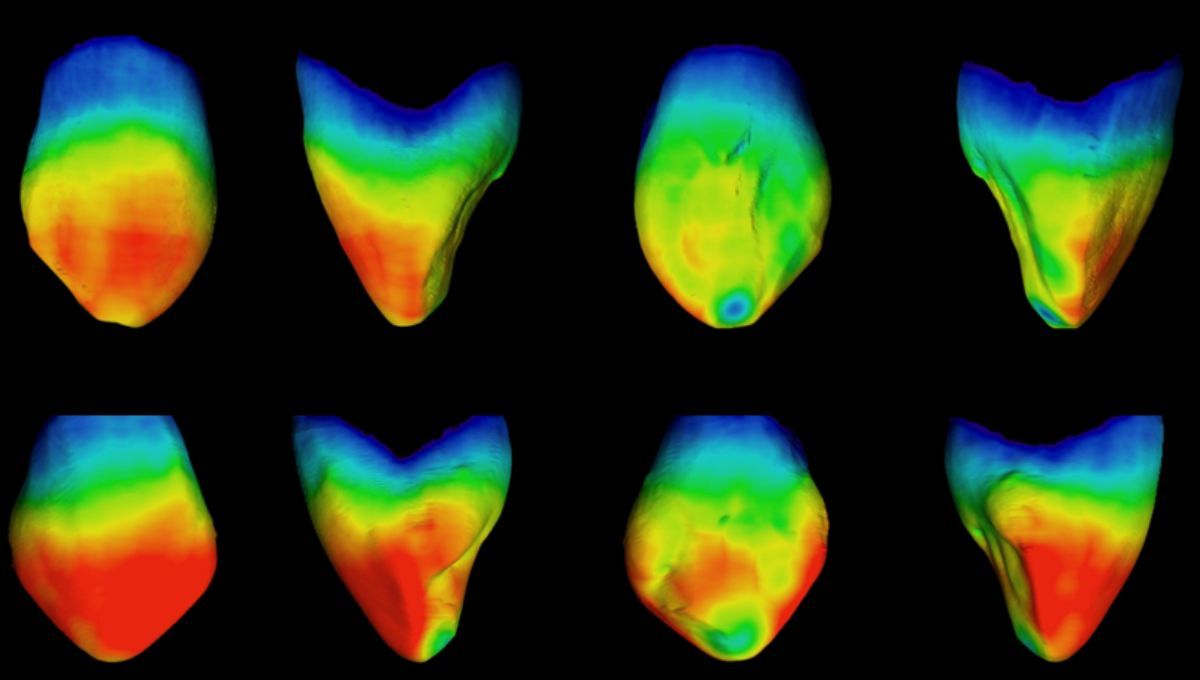

Gracias a la microtomografía axial computarizada (micro-CT) del Laboratorio de Microscopía y Microtomografía Computarizada del CENIEH, los autores han podido analizar las estructuras internas de la dentadura de ambas poblaciones, lo que les ha permitido apreciar diferencias en las dimensiones (absolutas y relativas) del esmalte y la dentina de los caninos. En este sentido, se ha podido observar que las poblaciones africanas tienen mayor cantidad de esmalte en sus piezas dentales.

El estudio ha permitido apreciar diferencias en las dimensiones absolutas y relativas del esmalte y la dentina de los caninos